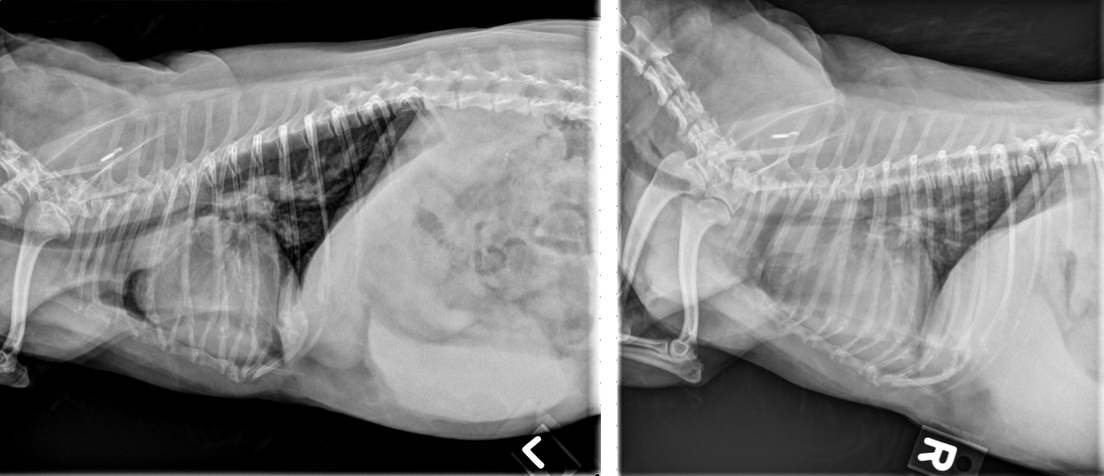

Dr. Anna Adrian, MS, DACVR, antwortet: Vielen Dank für die Zusendung dieses interessanten Falles. Es liegen eine links- und rechtslaterale sowie eine ventrodorsale Thoraxaufnahme vor. In allen drei Projektionen zeigt sich eine ausgeprägte rechtsseitige Kardiomegalie, die mit einer dorsalen Verlagerung der Trachea sowie einem vermehrten Kontakt des Herzens zum Sternum einhergeht (Bild 1, dunkelblaue Pfeilköpfe). In der ventrodorsalen Projektion imponiert die Rechtsherzvergrößerung als typische „reverse D-Form“ (Bild 2, dunkelblaue Pfeile). Zusätzlich fällt in dieser Ansicht auf Höhe der 2-Uhr-Position eine Vorwölbung auf, die einer Dilatation des Truncus pulmonalis entspricht (Bild 2, dunkelblauer Kreis).

Die kaudalen lobären Pulmonalarterien sind hochgradig erweitert, überschreiten deutlich die Breite der 9. Rippe und zeigen einen geschlängelten Verlauf (Bild 1 und 2, hellblaue Pfeile). Zur Erinnerung Venen liegen in der VD-Aufnahme zentral und in der lateralen Aufnahme ventral, wohingegen Arterien lateral und dorsal gelegen sind. Die Vena cava caudalis erscheint geringgradig dilatiert. Das Lungenparenchym weist insgesamt ein leicht- bis mittelgradig ausgeprägtes bronchointerstitielles Muster auf. Im kranialen Abdomen ist eine kraniale abdominale Organomegalie erkennbar, sowie geringgradige Heterogenität des abdominalen Fettgewebes (Bild 1, hellblau gestricheltes Rechteck). Dieser Befund ist vereinbar mit einer Splenomegalie +/- Hepatomegalie und geringgradiger Aszites. Die übrigen abdominalen Strukturen erscheinen unauffällig.

Zusammenfassend liegen eine ausgeprägte rechtsseitige Kardiomegalie sowie eine deutliche Erweiterung der Pulmonalarterien vor. Die Befundkonstellation spricht für eine pulmonale Hypertension in Kombination mit einer Kardiomyopathie, möglicherweise sekundär infolge einer Herzwurmerkrankung oder eines idiopathischen Cor pulmonale. Zur weiterführenden Abklärung wird eine echokardiographische Untersuchung empfohlen. Das bronchointerstitielle Lungenmuster kann altersphysiologisch bedingt sein, differentialdiagnostisch sind jedoch auch eosinophile Infiltrate im Rahmen einer parasitär bedingten Hypersensitivitätsreaktion in Betracht zu ziehen. Die Dilatation der Vena cava caudalis kann einerseits ein Normvariant darstellen, andererseits im Kontext der Rechtsherzvergrößerung auf eine Rechtsherzinsuffizienz oder ein Vena-cava-Syndrom bei hoher parasitärer Last hinweisen.